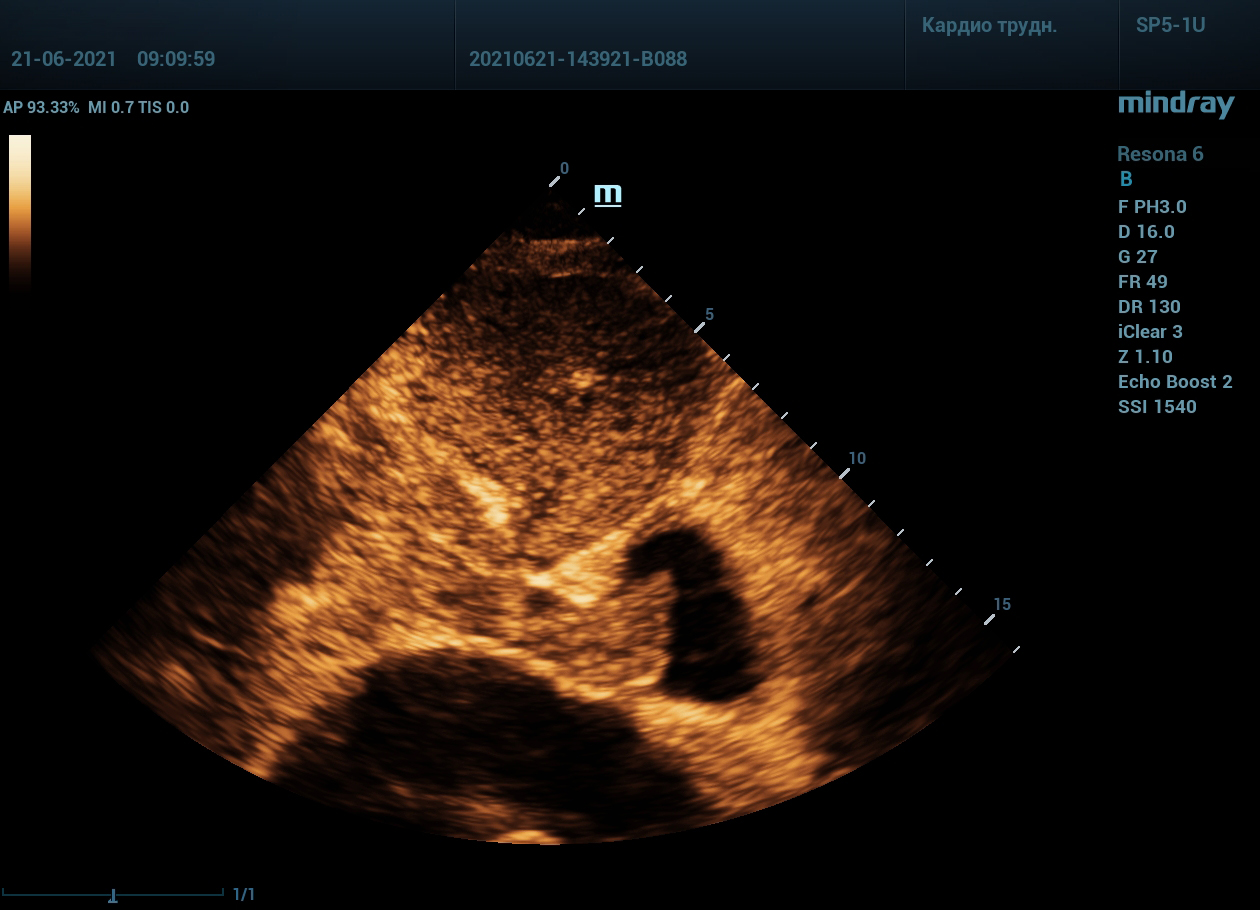

Интересный случай из практики нашего врача-аппликатора. Использовался экспертный ультразвуковой прибор Mindray Resona 6, стандартные заводские пресеты и автоматическая оптимизация iTouch. В эхокардиографии всегда помогает колорайзинг, чаще всего используется оранжевый оттенок. Пациент обследуется перед оперативным лечением по поводу онкологии почки. Вены нижних конечностей у данного пациента без особенностей, сжимаемы и проходимы. Казалось бы, проблема тромбоза миновала но в процессе эхокардиографического исследования, при сканировании нижней полой вены в субкостальном сечении, определяется эхогенное образование. Образование на месте просвета нижней полой вены. Вена расширена, эхогенное включение проникает в правое предсердие. По краю тромба в цветопотоковой визуализации определяется кровоток. Онкологическое заболевание почки осложнилось тромбозом почечной вены, с распространением тромба в нижнюю полую вену и правое предсердие. Изюминку добавляет то, что в других эхокардиографических сечениях тромб совершенно не виден.